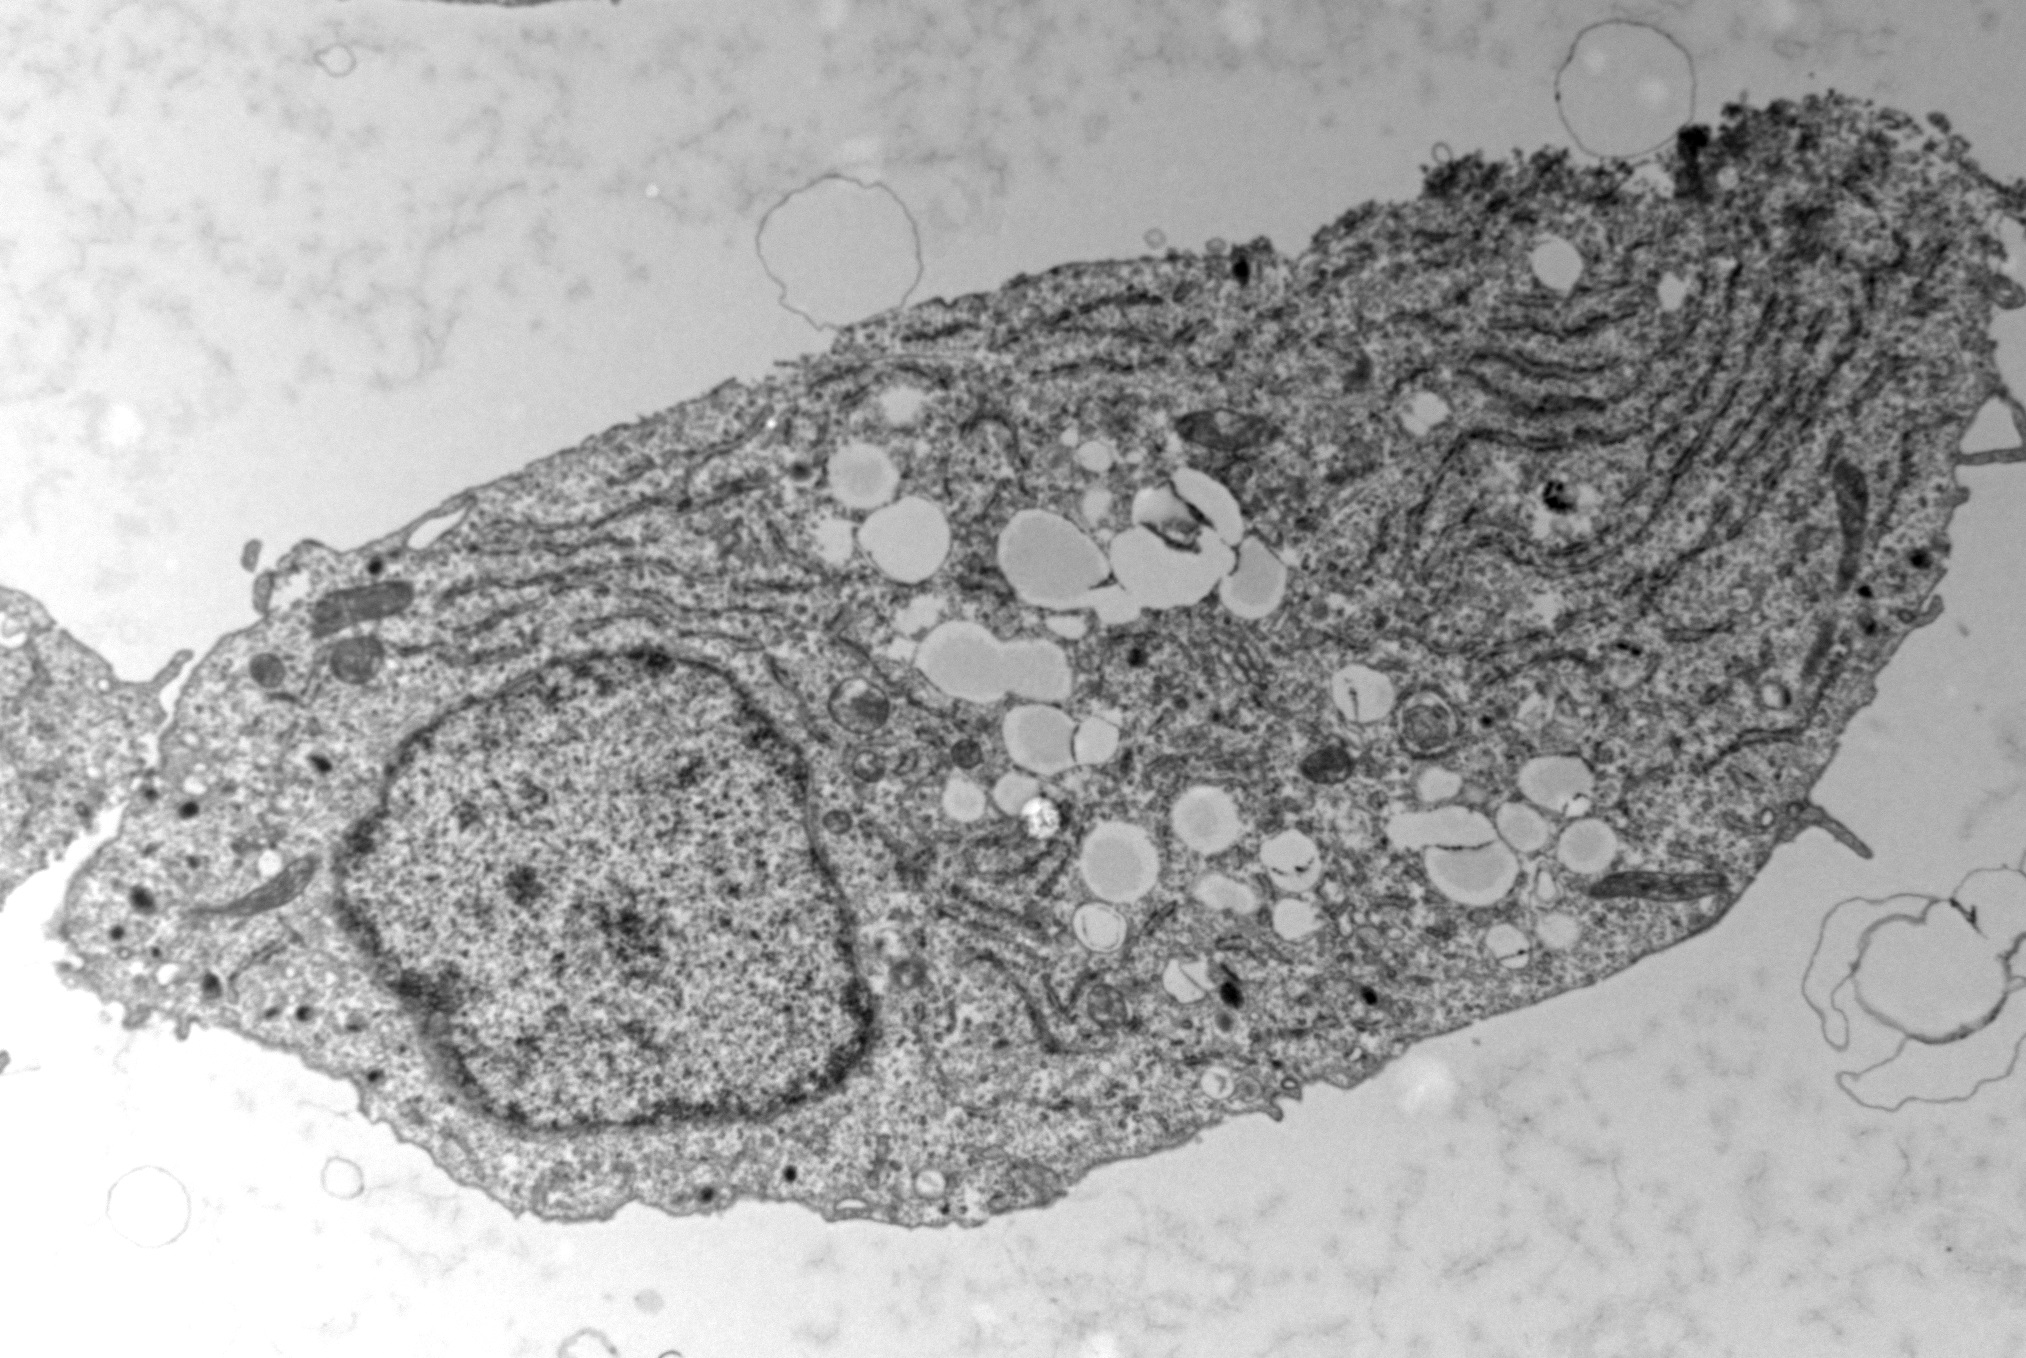

English below ----- Cellule bêta du pancréas en microscopie électronique. Les cercles blancs visibles au centre correspondent à des gouttelettes de stockage du gras. ----- Pancreatic beta cell under electronic microscopy. The white circles visible in the centre of the cell correspond to fat storage droplets.